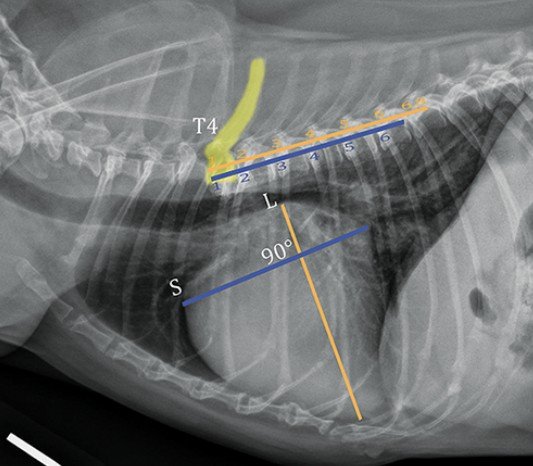

- Thoracic Radiographs (X-rays): Used to assess the “hemodynamic relevance” of the disease and check for fluid in the lungs (pulmonary edema).

Congestive heart failure on the Right x-ray